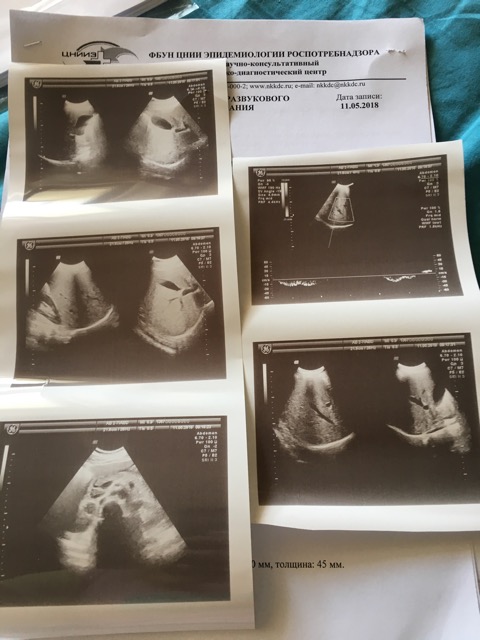

Утром сделала УЗИ, врач сказал по показателям все норм. За исключением печени( она увеличена).

Вложения

6B3ECC52-2EB4-47EF-960B-03B2015C421B.jpeg

8E7C2BA7-D536-46B5-8BB9-A8D935B75AF3.jpeg

да, печень увеличена